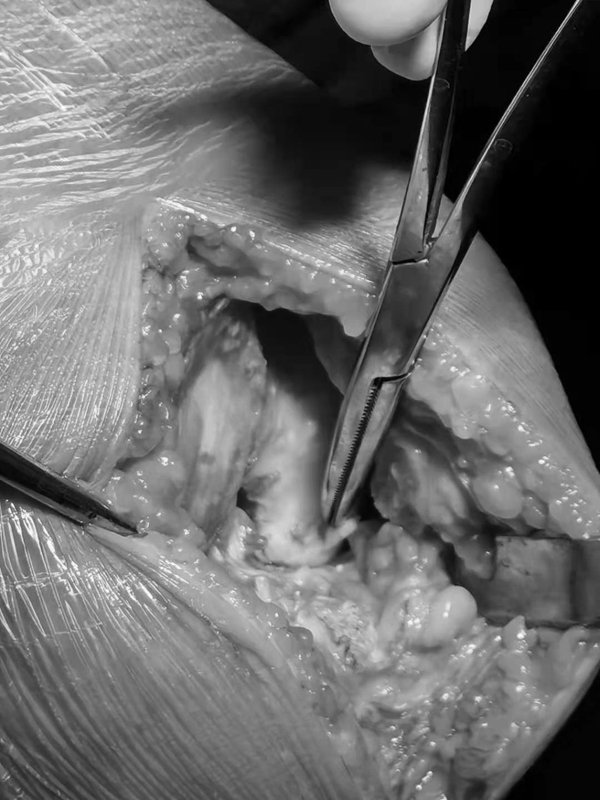

术中发现外侧小片软骨剥脱